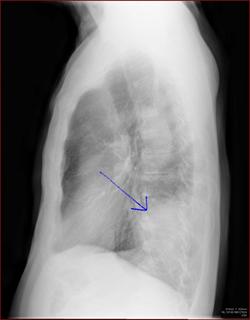

CTで見ると…

3Dだと、こうなります。

気管狭窄ですね。こういう所見もレントゲンで捉えることができるのです。